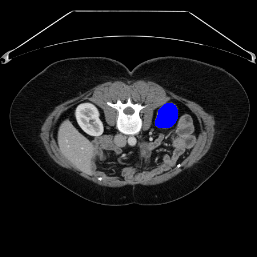

Support

Label

Proposed

In order to assess the performance of the proposed method, we compare the performance of the proposed model with excellent models in recent years. Table 1 and Table 2 shows the comparison results of different models in setting1, while Table 3 and Table 4 shows the comparison results of different models in setting2 on the data set in recent years. PANet[25] is the most widely influential few-shot model in the field of few-shot image segmentation on natural images. SENet [18] is the first few-shot segmentation model proposed for medical images. SSL-ALPNet[19] introduced the milestone of using superpixel self-supervision to train few-shot medical image models. RPNet[29] is a supervised method with a recursive mask optimization module to iteratively optimize the segmentation mask, [27] adapt it into the same self-supervision learning framework and applies setting1 to it and denoted as SSL-RPNet; CRAPNet[27] is the latest SOTA model for 2023. Compared with CRAPNet, our method outperforms most of the state-of-the-art models and only slightly outperforms CRAPNet. Figures 3 and 4 show examples of the model’s segmentation predictions on different datasets, respectively; The first row is the support map, the second row is the label map, and the third row is the segmentation prediction of the model.